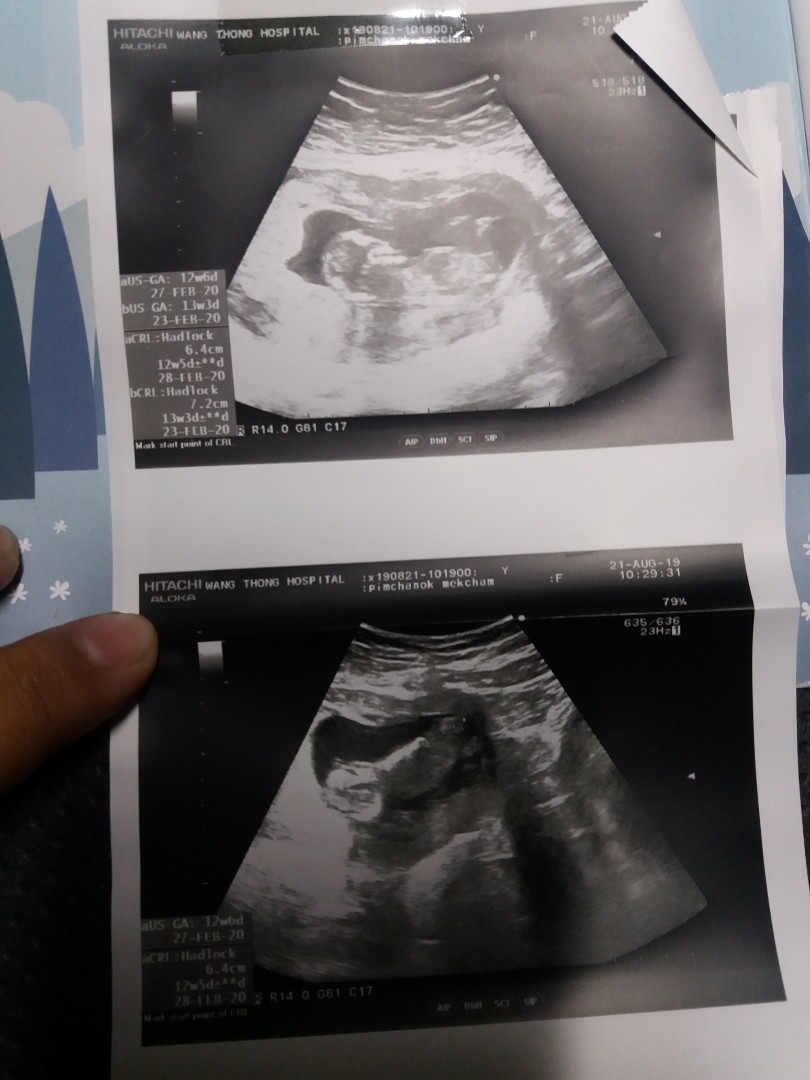

ลูกแฝด

เมื่อวานไปหาหมอก็มีเรื่องตกใจ ไปถึงวัดความดัน ปรากฏความดันสูง ได้ตรวจฉี่ พร้อมให้ตรวจเลือด แบบต้องรู้ผลวันนั้นเลย คือหมอบอกเสี่ยงครรภ์เป็นพิษ แต่ผลเลือดออกมาปกติ แค่เฝ้าระวัง และก็ยังมีเรื่องให้ดีใจ ตัวเล็กน้ำหนักดีมาก คนแรก 2800 คนที่สอง 2600 หมอบอกว่าเป็นแฝดที่ตัวใหญ่ดีนะ ได้ยินแบบนี้ดีใจมาก กำหนดผ่า 26 นี้ ตื่นเต้นมากอยากเจอหน้าเขาทั้ง 2 คนแล้ว